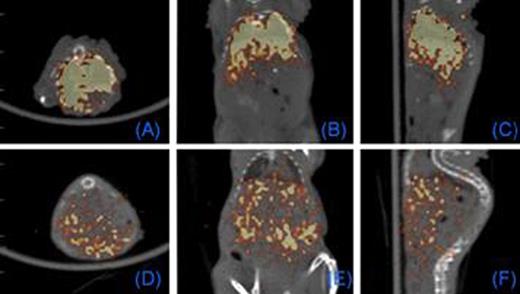

PET Imaging of T cells loaded with intracellular 64Cu-GNPs. 0.5 (A-C) and 18 (D-F) hours after tail vein injection of T cells. Each panel: axial, coronal, sagittal views, respectively.